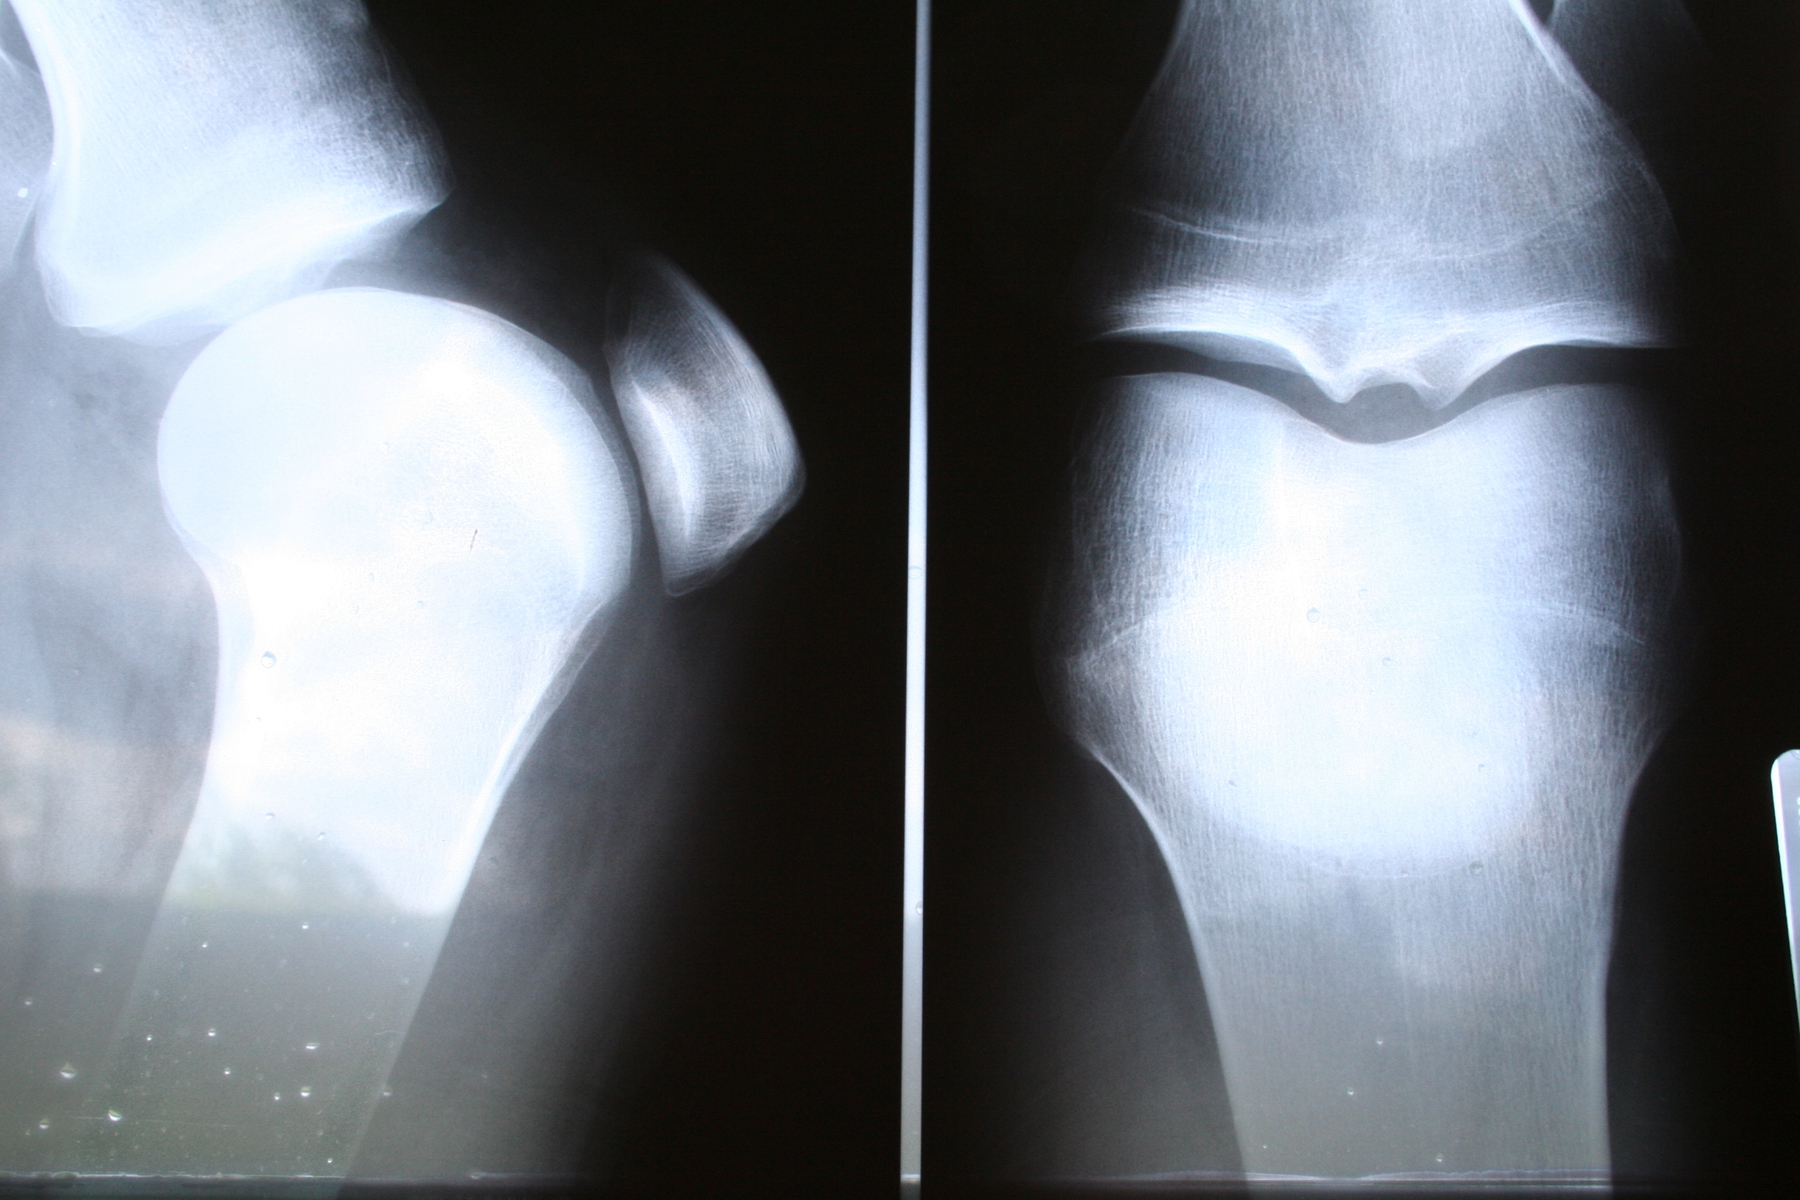

청구인은 2018년 2월 11일 공사 현장에서 문짝을 운반하던 중 사고로 인해 좌측 하퇴부 심부열상, 피부결손 및 괴사, 좌측 슬관절 염좌 등 다발성 부상을 입고 요양하던 중, 이후 좌측 발목 및 발 부위에 심한 통증이 지속되면서 복합부위통증증후군 1형(CRPS Type 1) 진단을 받고 추가상병을 신청하였습니다.

- 사고 당시 좌측 발 뒤꿈치에 문짝이 떨어져 하퇴부 및 슬관절 부위에 심한 외상이 발생.

- 치료 이후 좌측 발목 및 발 부위에 피부 온도 차이, 감각 과민, 운동 가동범위 감소, 색소 변화, 이질통 등의 증상이 지속됨.

- 주치의 소견서 및 대학교병원에서 시행한 QSART 검사 상 이상 소견 확인.